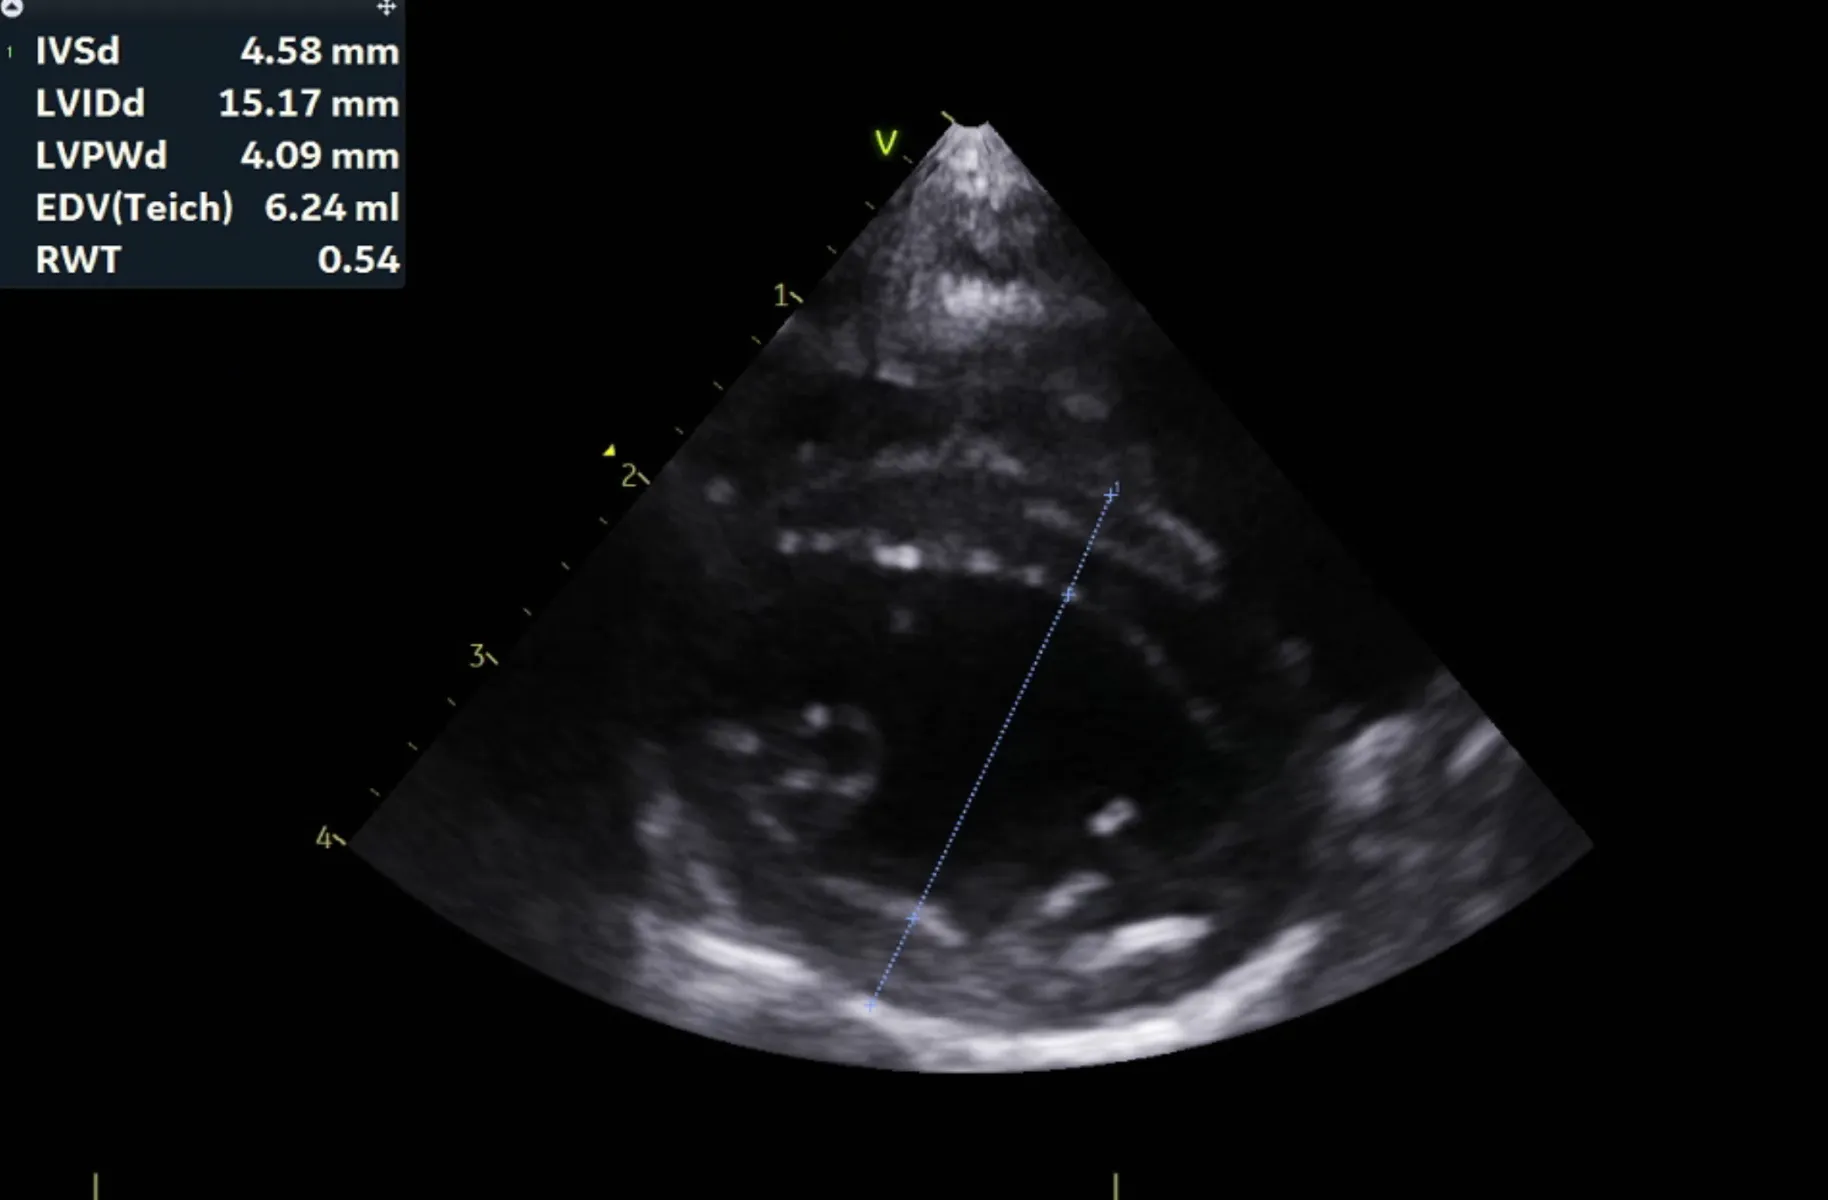

분류 수치

IVSd 4.66/4.58(2.80 - 4.90㎜) - 정상/정상

LVIDd 15.83/15.17(12.20 - 19.20㎜) - 정상/정상

LVPWd 4.21/4.09(2.80 - 4.80㎜) - 정상/정상

IVSs 6.06/5.17(4.30 - 8.40㎜) - 정상/정상

LVIDs 11.20/10.69(5.50 - 12.60㎜) - 정상/정상

LVPWs 4.66/5.02(4.60 - 8.50㎜) - 정상/정상

EF 59.9%/60.5%(40% - 67%) - 정상/정상

FS 29.3%/29.5%(30% - 49%) - 감소/감소

LVIDDN 0.98

EDVI 23(~100)

ESVI 9(~30)

Echo_comments

HCM으로 의심될만한 소견 관찰되지 않음

주치의 소견은 다음과 같습니다.

곰이 는 심장 초음파 검사 결과 현재 심잠벽의 두께는 정상이며 수축기능, 이완기능(심장이 정상적으로 잘 뛰는 것을 확인하는 검사) 모두 정상입니다.

심장 초음파는 1년에 한번씩 검사 받는 것을 추천드립니다.